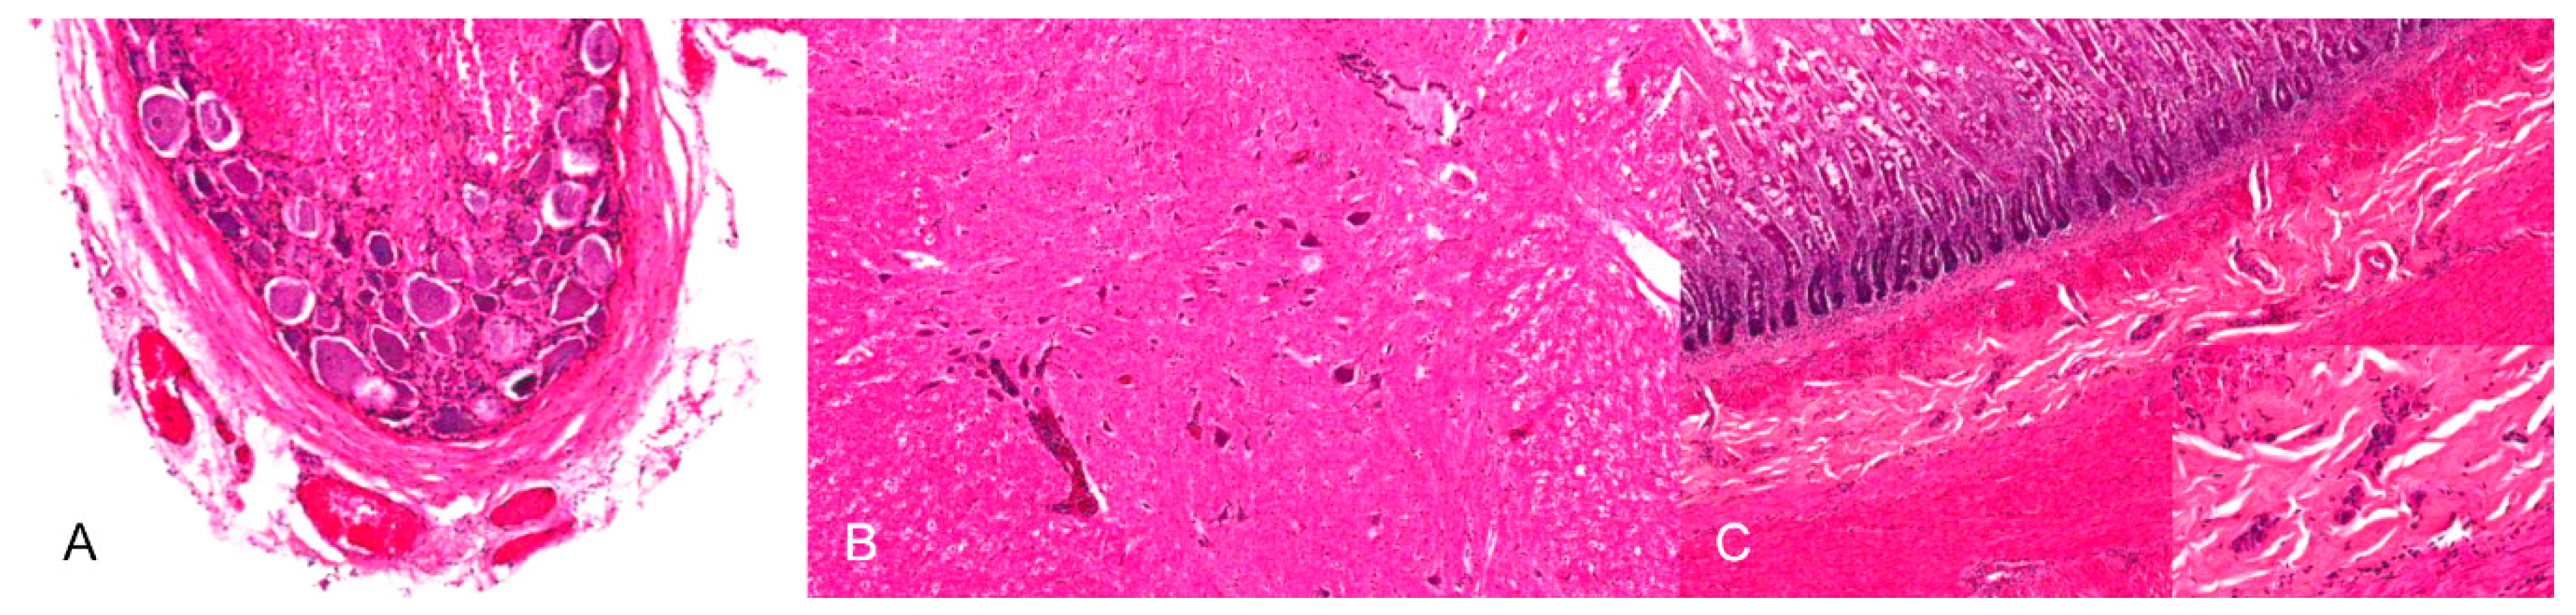

Neurotropic changes are seen in the brain, spinal cord as well as in spinal and vegetative ganglia as nonsuppurative, mainly lymphohistiocytic inflammation. The inflammatory response is characterized by neuronal necrosis and degeneration, neuronophagia and satellitosis as well as microglial activation and proliferation. Perivascular cuffs consisting of mainly lymphocytes, macrophages, and fewer neutrophils as well as meningeal infiltration are characteristic [44,46,48] (Figure 4). In piglets, panencephalitis is commonly present affecting the brainstem, cerebellum, thalamus and cerebrum including the olfactory bulb [28,44,46,48,52]. Principally, lesions are located in the grey matter, but can also involve the white matter [47,48]. Ganglioneuritis of the trigeminal, spinal, myenteric, submucous and mesenteric ganglia is common [28,43,47,52].

Figure 4.

Nonsuppurative meningoencephalitis in a PRV experimentally infected piglet. (A) Perivascular cuffs consisting of lymphocytes and histiocytes and mild microgliosis (inset). (B) Lymphohistiocytic infiltration of the adjacent meninges with few neutrophilic granulocytes, H.E. (Courtesy: Department of Pathology, University of Veterinary Medicine Hannover, Hannover).